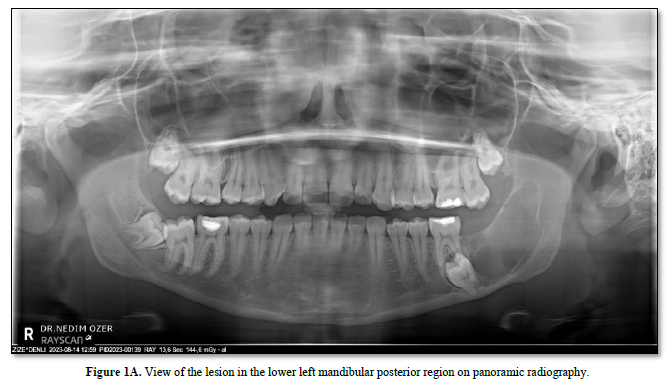

An 18-year-old female patient applied to our clinic with complaints of mild pain and paresthesia in her left lower jaw. As a result of the radiographic examinations (panoramic radiography, CT scan), a radiolucent, well-defined, non-expandable, two-compartment lesion was detected in the left posterior region of the patient's mandible, extending from the apical of tooth number 36 to the ramus. It was observed that the lesion, in which tooth number 37 was impacted at the apical part of tooth number 36, pushed the mandibular nerve inferiorly. There is no facial asymmetry or loss of function in the clinical examination of the patient. A biopsy was taken from the patient under local anesthesia and sent for pathological examination. As a result of the pathological report, it was determined that the lesion was Ameloblastic Fibroma. The patient was operated on under general anesthesia.

In the latest classification, WHO removed ameloblastic fibro-odontoma from the classification, considering it as an intermediate developmental stage of a tumor developing from ameloblastoma to odontoma. In this case, considering that we examined the entire tumor and that the dental hard tissue is seen in a very small focus and that fibroma and odontogenic-ameloblastic epithelium are determinants of morphology, it can be said that the prognostic process will be compatible with "Ameloblastic Fibroma" (Figures 1-3).